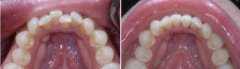

孩子牙齿拥挤可以做隐形矫正吗?

随着生活条件提高,食物越来越精细化,孩子的牙齿就会因为缺乏应有的锻炼,...【详细】

儿童牙齿拥挤问题严重吗?

经常接到类似的咨询,说孩子前牙比较不齐,应该属于拥挤那一类的,请问这种...【详细】